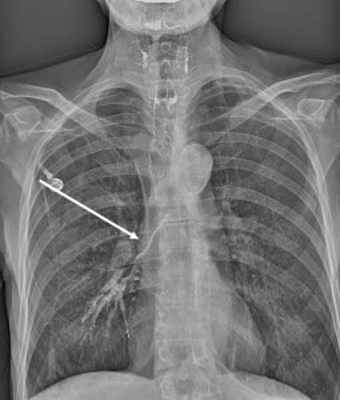

При поступлении предъявляла жалобы на общую слабость, снижение аппетита, одышку при физической нагрузке, повышение температуры до 37,8 °С. При обзорной рентгенографии легких (рис. 3, а) Рис. 3. Данные обследования больной Г. до операции. а — обзорная рентгенограмма органов грудной клетки (слева определяется субтотальная туберкулезная эмпиема плевры); б — компьютерные томограммы органов грудной клетки (в левой плевральной полости заднекостально располагается массивное осумкование густой жидкости). 20.11.07 выполнена ВАТС-плеврэктомия слева с декортикацией легкого (хирург Д.Б. Гиллер). слева определяется осумкованная эмпиема плевры. На компьютерных томограммах (см. рис. 3, б) в задних отделах левой плевральной полости массивное осумкование с выраженным уменьшением объема левого гемиторакса.